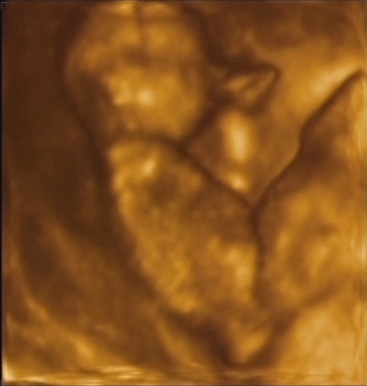

. Az ifjú anyukákat megértem (Réka, Inari, Melba), ilyen pici csomagocskával még én sem mertem annó elindulni. De a decemberi Gigi-bulin már biztosan láthatjuk őket is! De addig is, hadd tanuljon valami ügyeset a manócskám a medvécskédtől

Ő is vár mindenkit szeretettel: